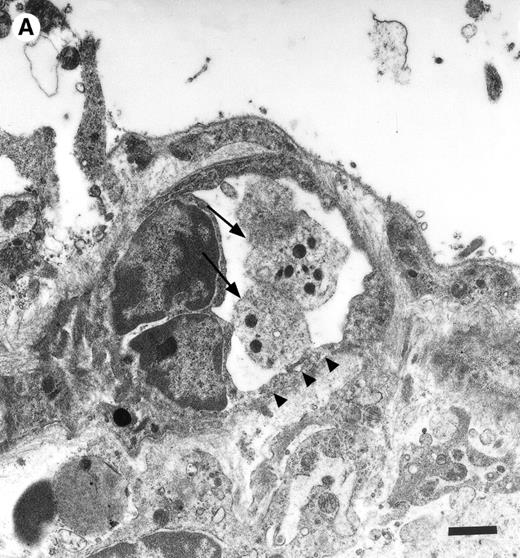

To assess fibrinogen deposition during I/R, the vascular distribution of fibrinogen was determined using immunohistology. In sham-operated animals small amounts of fibrinogen were detectable within the vessel lumen. Fibrinogen accumulation on the endothelial surface was not observed. In contrast, fibrinogen sequestration on the luminal surface of arterioles and venules was a prominent phenomenon after I/R. To investigate the time course of fibrinogen binding to the endothelial cell surface during I/R in vivo, fluorescent fibrinogen was administered intravenously before the induction of 1.5 hours of ischemia. In the physiologic state (baseline conditions), Alexa 488-conjugated fibrinogen was found homogeneously distributed in the plasma. No fibrinogen deposition was detectable in arterioles or venules (Fig 4). Similarly, during the ischemic period, no significant accumulation of fibrinogen on the endothelial surface was observed. In contrast, reperfusion dramatically enhanced fibrinogen binding to the endothelium in the postischemic microvasculature. Within 1 to 5 minutes after the onset of reperfusion, streaks of fluorescent fibrinogen were observed along the endothelial lining. After 10 minutes of reperfusion, the gaps between the streaks were partially filled with fibrinogen, resulting in a heterogenous fibrinogen coat on the endothelial cell surface of the majority of all vessels studied. In most instances, significant fibrinogen deposition at the arteriolar and venular endothelial surface coincided with the adhesion of platelets in these areas (Fig 4).

Accumulation of fibrinogen and platelets during I/R in vivo. Alexa 488-conjugated human fibrinogen (17 mg/kg) was administered intravenously 30 minutes before the induction of ischemia (left column). Rhodamin-labeled platelets were visualized in identical arterioles and venules using a different filter set (right column; see Materials and Methods). In wild-type animals (A,B), fibrinogen is bound unevenly to the vascular wall of arterioles and venules in the postischemic microvasculature. Areas with large amounts of fibrinogen (A, large arrow) can be seen besides regions without detectable fibrinogen deposition (A, small arrow). The accumulation of large amounts of fibrinogen colocalizes with platelet adhesion (B, arrowhead). In mice lacking ICAM-1 (C,D), the I/R-induced accumulation of fibrinogen and platelets is attenuated. Monitor magnification, 450×.

To determine the role of ICAM-1 as an endothelial fibrinogen receptor, the accumulation of Alexa 488-conjugated fibrinogen during I/R was investigated in mice deficient in ICAM-1. No fibrinogen binding was seen under control conditions or during ischemia. During reperfusion, a moderate increase in endothelial fibrinogen binding occurred in few arterioles and venules (Fig 4), while the majority of the vessels studied showed no significant fibrinogen accumulation, indicating that ICAM-1 is in fact involved in mediating the deposition of fibrinogen at the postischemic endothelium. To evaluate whether ICAM-1–dependent fibrinogen sequestration on the endothelial surface might mediate platelet-endothelial cell interactions during postischemic reperfusion, fluorescent wild-type platelets were infused into ICAM-1–deficient animals (Fig 1). Whereas the number of rolling platelets did not differ from wild-type mice (23 ± 5 and 36 ± 4 platelets/s/mm in arterioles and venules, respectively), platelet adhesion was significantly reduced in the absence of endothelial ICAM-1: 125 ± 42 and 71 ± 27 platelets were seen firmly attached per mm2 endothelial cell surface of arterioles and venules, respectively, indicating that ICAM-1 is in fact involved in platelet recruitment during postischemic reperfusion.